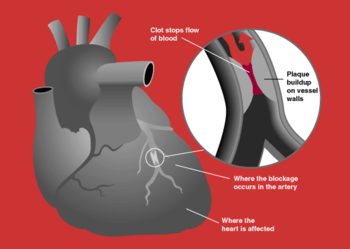

A heart attack, known in medicine as an (acute) myocardial infarction (AMI or MI), occurs when the blood supply to part of the heart is interrupted. This is most commonly due to occlusion (blockage) of a coronary artery following the rupture of a vulnerable atherosclerotic plaque, which is an unstable collection of lipids (like cholesterol) and white blood cells (especially macrophages) in the wall of an artery. The resulting ischemia (restriction in blood supply) and oxygen shortage, if left untreated for a sufficient period, can cause damage and/or death ( infarction) of heart muscle tissue ( myocardium).

Pathophysiology

Acute myocardial infarction refers to two subtypes of acute coronary syndrome, namely non-ST-elevated myocardial infarction and ST-elevated myocardial infarction, which are most frequently (but not always) a manifestation of coronary artery disease. The most common triggering event is the disruption of an atherosclerotic plaque in an epicardial coronary artery, which leads to a clotting cascade, sometimes resulting in total occlusion of the artery. Atherosclerosis is the gradual buildup of cholesterol and fibrous tissue in plaques in the wall of arteries (in this case, the coronary arteries), typically over decades. Blood stream column irregularities visible on angiography reflect artery lumen narrowing as a result of decades of advancing atherosclerosis. Plaques can become unstable, rupture, and additionally promote a thrombus (blood clot) that occludes the artery; this can occur in minutes. When a severe enough plaque rupture occurs in the coronary vasculature, it leads to myocardial infarction (necrosis of downstream myocardium).

If impaired blood flow to the heart lasts long enough, it triggers a process called the ischemic cascade; the heart cells die (chiefly through necrosis) and do not grow back. A collagen scar forms in its place. Recent studies indicate that another form of cell death called apoptosis also plays a role in the process of tissue damage subsequent to myocardial infarction. As a result, the patient's heart will be permanently damaged. This scar tissue also puts the patient at risk for potentially life threatening arrhythmias, and may result in the formation of a ventricular aneurysm that can rupture with catastrophic consequences.